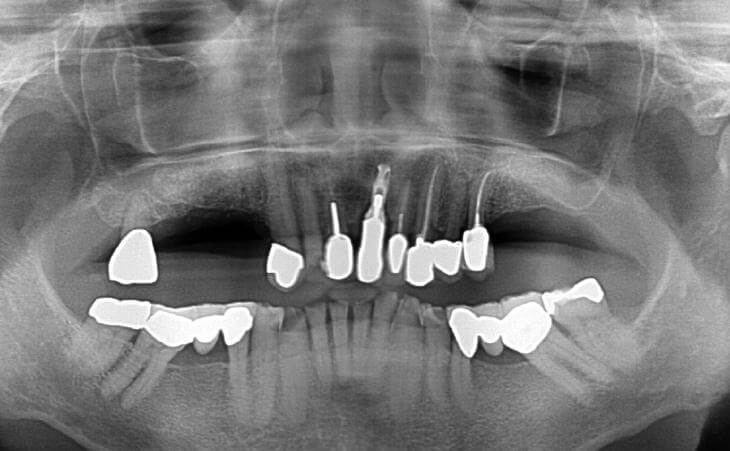

Patient presented with multiple areas of right and left upper jaw tooth loss for years and subsequent bone resolution. The patient underwent bilateral sinus lift procures and ridge grafts for future implant placement

Patient has been missing right and left upper teeth for many years. Bone has deteriorated and a CT scan showed insufficient bone volume for implant placement. The patient underwent Bilateral Sinus Lift surgery and Bone regeneration.

Patient has been missing all her upper teeth and has worn an upper denture for the past 20+ years. The patient underwent Bilateral Sinus Lift surgery and Bone regeneration.

44 year old male missing right and left upper teeth for years decided to have implants placed to replace his upper denture. CT scan determined there was advanced bone loss in the upper jaw under his sinus cavities. Bilateral Sinus Lift Bone Graft was performed for implant placement.